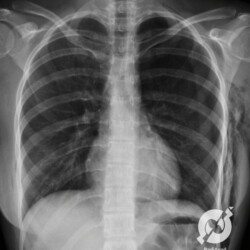

Pneumotórax bilateral de pequeno volume pós-simpatectomia. Caso difícil. Não viu? Não tem problema, o negócio é treinar e se acostumar com a imagem.